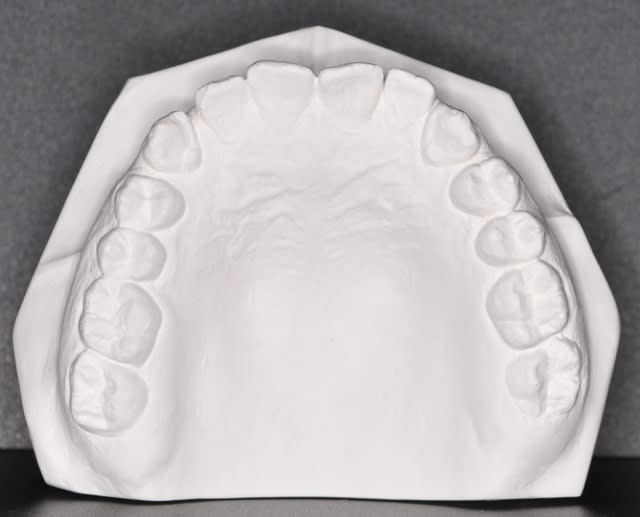

les dernieres photos du cas

Pour moi la mandibule est correcte dans le sens transversal et le problème se situe au niveau du coté maxillaire gauche

Tu as raison, c'est bien le maxillaire qui semble en exo à gauche.

Tu as aussi certainement, associée, une mastication unilatérale à droite.

-l'asymétrie dento-alvéolaire supérieure par rapport au visage

-la symétrie de l'axe inter incisif par rapport au frein lingual

-la persistance du même décalage des axes inter incisif lors de la grande ouverture